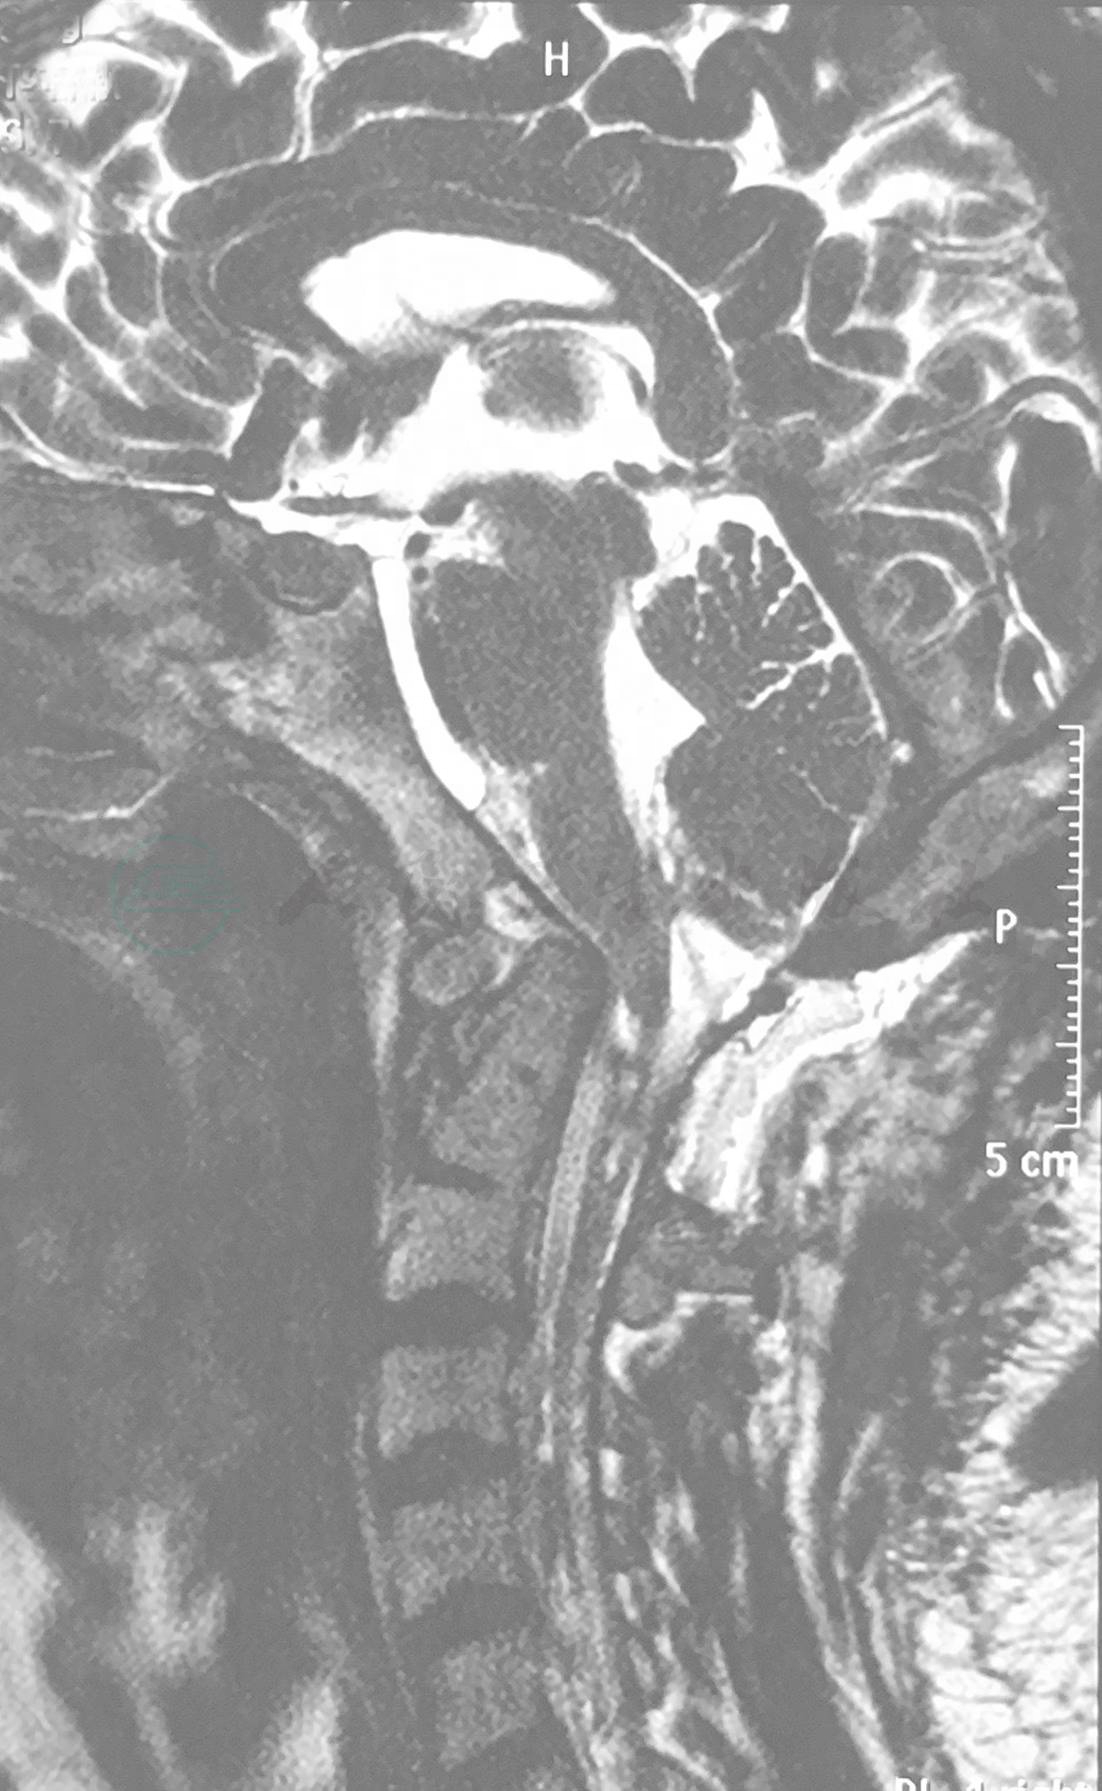

2013年5月行磁共振(MRI)示小脑扁桃体下疝,伴随脊髓空洞(图1)。2013年6月头颅CT示脑室系统扩张明显(图2)。2014年1月复查头颅CT符合脑室腹腔分流术后改变,脑室系统无扩张(图3)。2016年5月颈部磁共振(MRI)示小脑扁桃体下疝畸形术后改变,脊髓空洞较前明显增大(图4),脑脊液电影示桥前池、第四脑室出口脑脊液流动信号弱。中脑导水管、第四脑室及枕骨大孔后部脑脊液流动信号弱(图5)。颈椎CT示齿状突上移,超过Chamberlain线上,寰齿椎间隙扩大,考虑颅底凹陷合并寰枢椎半脱位(图6),三维重建示枕骨及寰椎后弓缺失(图7)。

图1 2013年5月第一次术前磁共振(MRI)

a.T1像;b.T2像